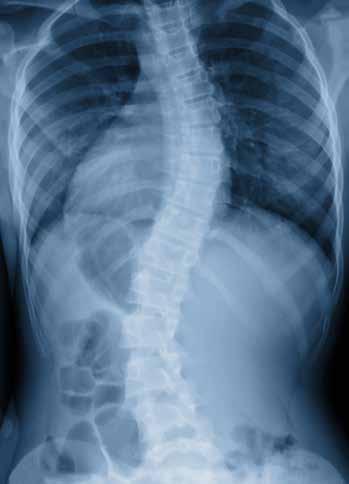

DR. DANIEL KRAUS COMBINES ADVANCED BIOMECHANICS WITH PRECISION SPINAL CARE

Dr. Daniel Kraus, DC, owner and clinical director of Bethesda Spine & Posture in Bethesda Row, is not your typical chiropractor. Practicing since 1997, Dr. Kraus has developed one of the region’s most advanced non-surgical spinal rehabilitation program, an approach he describes as “a specialty within a specialty within a specialty.”

He is one of only a handful of chiropractors in Maryland who hold an Advanced Certification in Chiropractic BioPhysics® (CBP), the most researched and results-driven method for structural correction of the spine.

What truly sets his practice apart, however, is the integration of ScoliCare® protocols, including ScoliBrace® and ScoliBalance®—for the non-surgical management of scoliosis, kyphosis, and postural deformities. This unique combination of CBP structural correction and ScoliCare 3D bracing represents a comprehensive, evidence-based approach to restoring alignment, stability, and function.

Scoliosis and Spinal Deformity Expertise

Dr. Kraus specializes in the conservative treatment of adult and adolescent scoliosis, kyphosis, and spondylolisthesis— conditions that can cause pain, fatigue, and progressive spinal collapse. His goal, he explains, is simple but ambitious: “These are collapsing deformities of the spine— and our mission is to stop that collapse.”

At Bethesda Spine & Posture, patients receive individualized care plans that may include CBP corrective traction, posture-specific exercise, and custom ScoliBrace® 3D bracing. Each brace is designed using a patient’s X-rays, photos, and 3D iPad scans, ensuring an exact fit that promotes spinal elongation, midline alignment, and de-rotation.

“People are amazed at how much taller, straighter, and more balanced they feel almost immediately,” says Dr. Kraus. While adolescents may wear the brace up to 22 hours daily during growth phases, adults typically use it for 4–8 hours a day as part of a broader posture restoration plan.